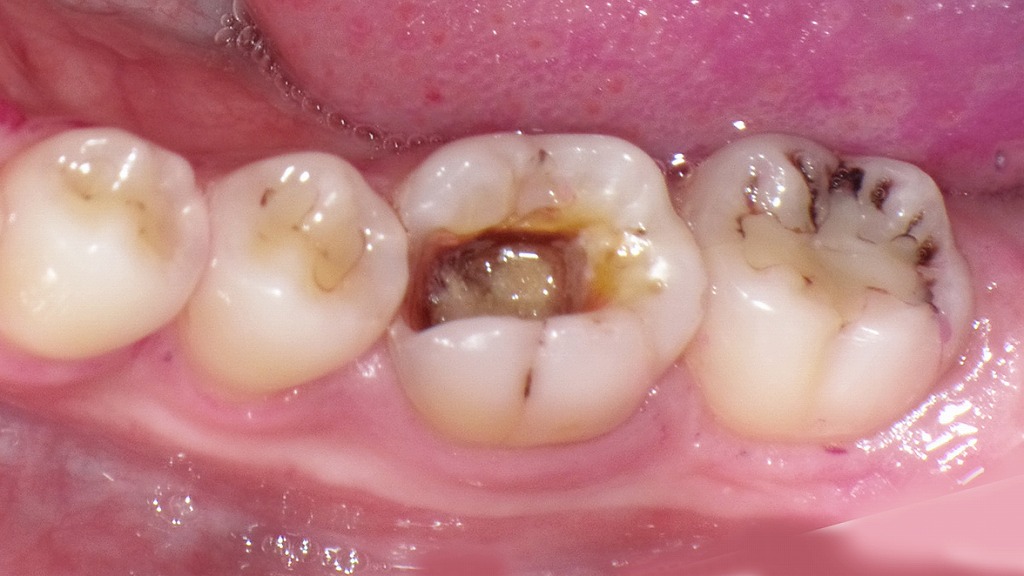

この写真は下顎左側の臼歯部(6番を中心)を示しています。以下に詳細を解説します。

🦷 状況の概要

中央の**下顎第1大臼歯(6番)**に注目すると、インレー(詰め物)が脱離しており、歯の内部に黒褐色の虫歯(カリエス)が確認されます。象牙質が露出しており、中心部には変色した軟化象牙質が残存しています。

🩺 臨床所見

- 歯種:下顎左側第1大臼歯(6番)

- 状態:金属インレー脱離後、う蝕再発(C2程度)

- 症状:

- 自発痛なし(常時の痛みはない)

- 冷たいものにしみる(冷刺激痛:可逆性歯髄炎の可能性)

- 食片圧入あり(隣接面の開放)

🧬 診断推定

- 診断名:C2(象牙質う蝕)

- う蝕範囲:咬合面中心部〜近心辺縁隆線部

- 歯髄反応:生活歯、冷水痛あり(軽度)

- 歯周組織:歯肉は軽度の発赤を認めるが、明らかな腫脹や排膿はなし

💡 治療方針(例)

- う蝕除去・感染象牙質の清掃

- 歯髄の状態確認

→ 生活反応があれば保存的修復 - 再修復

- コンポジットレジン充填(CR修復)または

- インレー再製作(金属またはセラミック) - 隣接面閉鎖による食片圧入の改善

- 再発予防指導(プラークコントロール・フロス使用)

📋 注意点

このまま放置すると、う蝕がさらに進行しC3(歯髄炎)→根管治療が必要になる可能性があります。

現在の段階(C2)での早期処置が、歯の保存と治療の簡便化につながります。